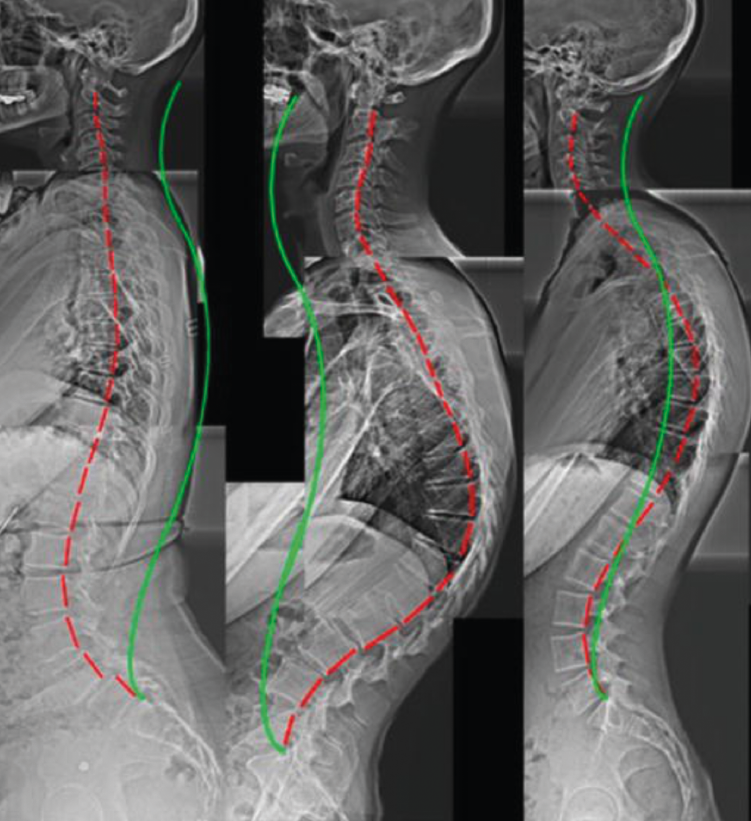

Otros hallazgos radiológicos frecuentes, como las anomalías congénitas de transición lumbosacra, espondilolistesis, secuelas de epifisitis, la espina bífida oculta, las escoliosis leves o moderadas, la hiperlordosis, espondiloartropatía, etc., se encuentran casi por igual en pacientes con y sin dolor lumbar (Figuras 5, 6 y 7)(22,23).

La más frecuentemente utilizadas son la proyección AP y L. Se debe procurar incluir al menos hasta T11 y el borde superior de las caderas (Figura 8).

Las radiografías oblicuas no son necesarias de forma rutinaria, estando indicadas en pacientes con una elevada sospecha de presentar una espondilólisis (Figura 9).

Las radiografías dinámicas, habitualmente empleadas para descartar la presencia de una inestabilidad vertebral, no deben realizarse nunca en la fase aguda del dolor lumbar.